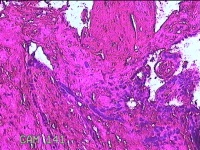

子宫腔内容物

性别

女

年龄

33岁

临床诊断

异常子宫出血;药流不全?宫腔占位

一般病史

阴道流血9天。

标本名称

大体所见

灰白暗红色不规则碎组织1.5x1x0.3cm一堆,未发现明显的绒毛样组织。

图1

不具诊断价值。